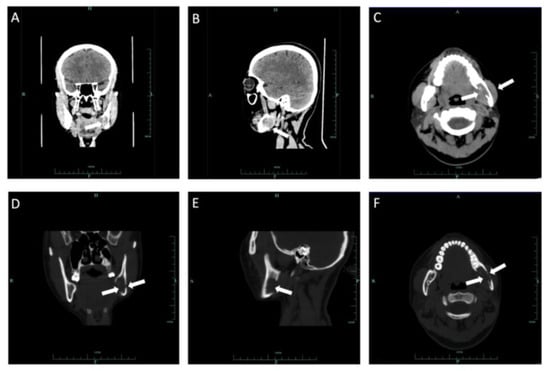

2.1. Case 1